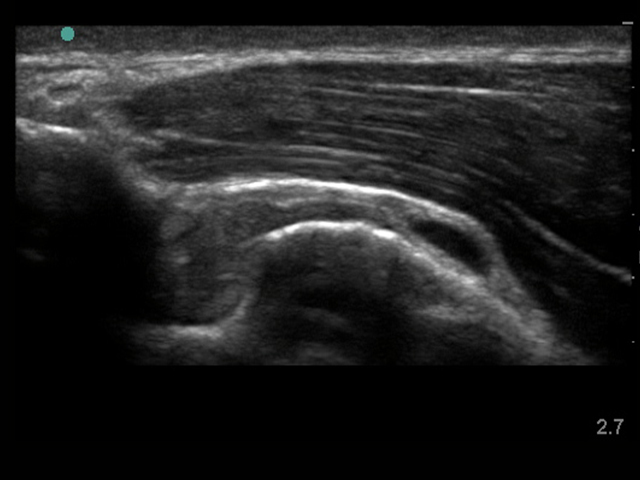

Shoulder Subdeltoid Bursal Thickening Neutral Image